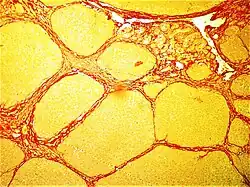

Healthy myocardium versus interstitial fibrosis in dilated cardiomyopathy. Alcian blue stain.